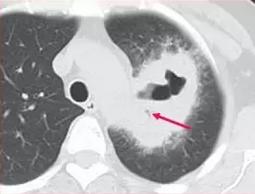

幸运1,女性,56岁,反复咳嗽、咳痰2个月,胸部CT发现左肺不规则厚壁空洞:

虽然是大肿块伴有大空洞,但空洞壁发现平行的支气管,这提示肺脓肿,进一步增强CT检查:

空洞壁均匀强化,也倾向于炎症性病变。

后来抗炎治疗吸收了,证实这也是一例肺脓肿,不是肺癌。